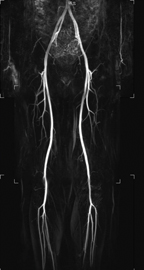

MRIはCTやX線撮影では分からない脳梗塞や、動脈瘤を可視化することができるため、脳卒中患者様においては重要な検査となっています。さらに、神経、靭帯、前立腺胆管、膵管などもよく分かるため、さまざまな診療科で需要は非常に高いです。